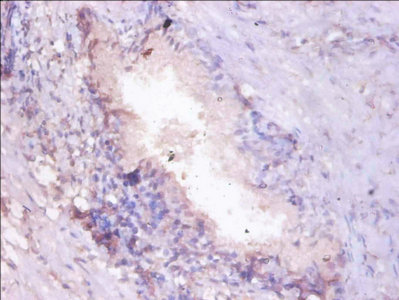

Immunohistochemistry of paraffin-embedded human prostate cancer using CSB-PA01335A0Rb at dilution of 1:100